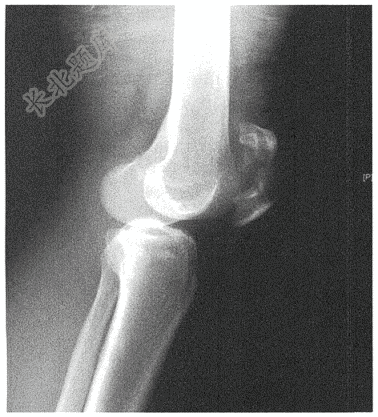

- 简答题患者男性,32岁,左膝外伤1小时。查X线如下:

- 男性,32岁( )